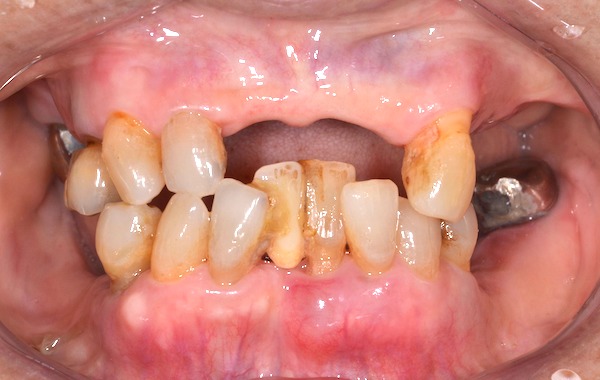

患者様は70歳女性、主訴は「入れ歯をひっかけていた左上の差し歯が取れてしまった。入れ歯の見た目が悪いので、できたら見た目もなんとか綺麗にしたい。今回、時間ができたので、徹底的に治療したい!」というものでした。

患者様のお口の状態は、歯周病がかなり進行しており、表から見えるところに、入れ歯のバネが多数かかっていました。